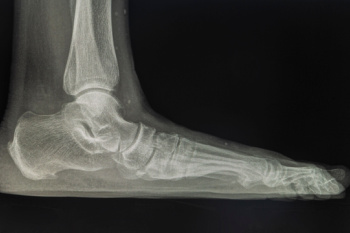

Flatfoot occurs when the arches of the feet collapse or never fully develop, causing the entire sole to touch the ground when standing. This condition can appear in childhood or develop later in life due to injury, arthritis, or wear and tear on the posterior tibial tendon, which is the tendon that supports the arch of the foot. Flatfoot may cause aching in the arches or heels, swelling along the inside of the ankle, and fatigue after long periods of walking or standing. Over time, the altered alignment can place extra stress on the knees, hips, and lower back. Wearing supportive footwear, custom orthotics, and stretching exercises for the calves and Achilles tendon can provide relief and improve function. In more advanced cases, bracing or surgery may be required to restore alignment. If you are experiencing persistent discomfort or difficulty from flatfoot, it is suggested that you see a podiatrist for a thorough evaluation and an appropriate treatment plan.

Flatfoot is a condition in which the arch of the foot is depressed and the sole of the foot is almost completely in contact with the ground. About 20-30% of the population generally has flat feet because their arches never formed during growth.